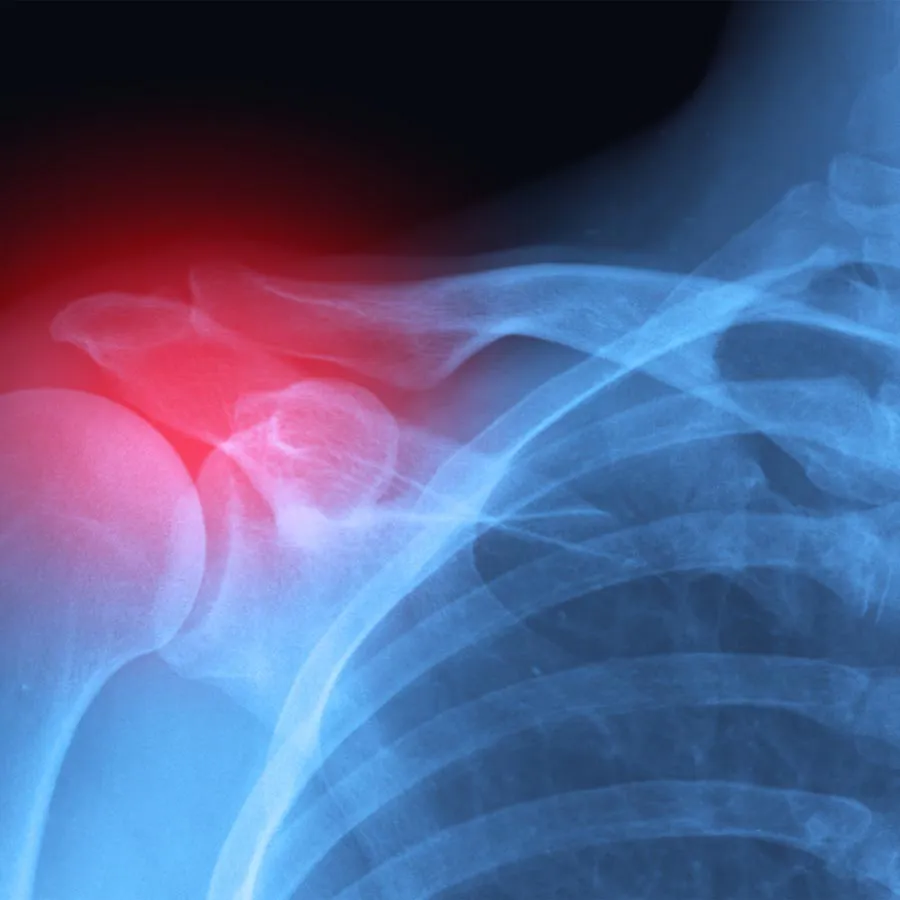

Shoulder Pain

Shoulder pain can show up in many forms – dull aches, sharp pinches, reduced range of motion, or weakness that makes lifting or reaching difficult. While it’s easy to assume it’s just overuse or a minor strain, shoulder pain often points to deeper issues with posture, joint instability, or nerve interference that start in the spine or neck. Without proper care, these problems can persist or worsen over time.